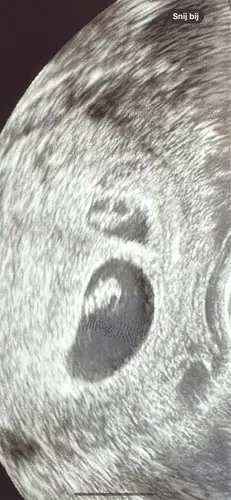

Ik vind het erg spannend. Het verschil in lengte is klein (1 dag) maar de zak van baby A was wel 2 a 3x zo groot als Baby B. Ik merkte dat de VK het zorgelijk vond.. poe! Ik vind het heftig. Fijn om te horen dat er positieve uitkomsten zijn